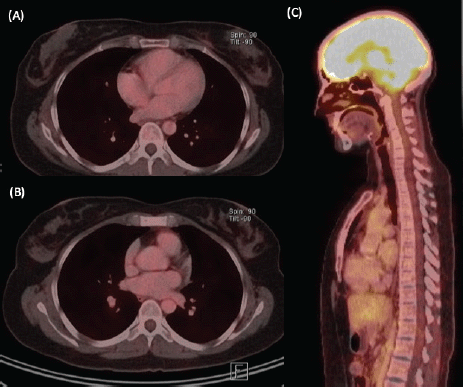

We present the case of a 36-year-old woman, with insulin resistance, without a family history of breast cancer, who consulted for a 6-month evolution self-detected left breast nodule associated with skin retraction. At the physical exam, there was a 20-mm palpable mass retracting the skin at the lower-inner quadrant (LIQ) of the left breast, without clinically evident axillary adenopathies. The patient was studied with mammography [Figure 1] and breast ultrasound [Figure 2], which showed a spiculated mass of 29 × 24 × 14 mm at the LIQ of left breast, with the increased flow at doppler, diagnosed as BIRADS-5. A core biopsy was performed, demonstrating a poorly differentiated invasive ductal carcinoma with positive oestrogen receptor (99%; / ), positive progesterone receptor (90%; ), positive human epidermal growth factor receptor type 2 (HER2) 3 , fluorescence in situ hybridisation for HER2 and Ki-67 30%. The staging study demonstrated an osteolytic lesion compatible with sternal metastasis evident in computed tomography (CT), positron emission tomography (PET)/CT and magnetic resonance imaging (MRI) [Figure 3]. The staging was completed with sentinel lymph node biopsy, obtaining six lymph nodes without metastasis. The primary lesion was marked with two metallic clips guided by ultrasound. The patient completed neoadjuvant ST with Doxorubicin, Cyclophosphamide, Paclitaxel, and HER2-directed therapy with Trastuzumab and Pertuzumab, with a complete clinical response at physical exam and images [Figure 4]. Later, she underwent left partial mastectomy, using percutaneous hookwire for the location of the metallic marker clips. The definitive biopsy demonstrated an area of 27 × 25 × 15 mm of scarring substitutive fibrosis associated with isolated microfocus (less than 1 mm) of moderately differentiated invasive ductal carcinoma with negative margins. The study of residual tumour load reported 1% invasive carcinoma and 0% intraductal carcinoma in situ. Two months after the surgery, LT with radiotherapy was completed. The breast was treated with tangential X-ray fields of 6 and 18 MV, the supraclavicular and left axillary region with a right anterior oblique field, and the internal mammary territory and sternum with an array of photons of 18 MV and electrons of 9 MeV, completing in all areas a dose of 50 Gy in 25 fractions in 5 weeks and then a boost of 10 Gy in 5 fractions over the tumour bed. Subsequently, it was decided to complete ST with Trastuzumab and Pertuzumab, in addition to pharmacological ovarian suppression with Triptorelin plus Tamoxifen. The HER2-directed therapy will be maintained until the progression of the disease or toxicity.

Figure 4. Re-staging imaging study, after 6 months of ST. (A) Axial view of PET/CT with size decrease and hypermetabolism resolution at the left breast nodule. (B) Axial and (C) sagittal views of PET/CT showing hypermetabolism resolution at the sternal body lesion.